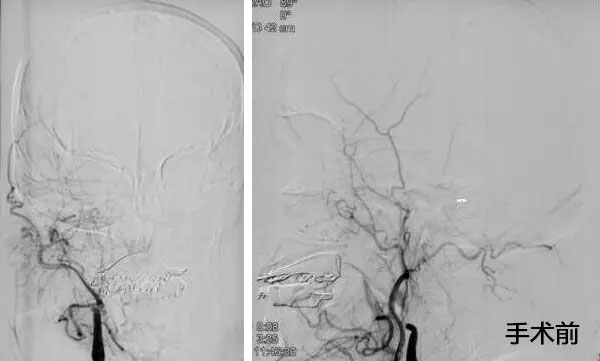

▲ 患者取栓前后DSA造影图

10:00am,患者被送入手术室,全麻下行全脑血管造影示:右侧颈内动脉处血流完全闭塞,血栓位于右侧颈内动脉T型分叉部,其他血管代偿不好,必须及时取栓干预。将微导管、微导丝送达血栓远瑞,微导管、微导丝到位后,成功释放支架,多次抽吸+支架拉栓,历时三个小时,取出大量血栓,患者血管达到2B级开通,血管恢复了供血。术后,转入九楼ICU。目前患者状态平稳,正在康复中。